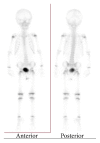

Background. Ewing sarcoma (ES) is a high-grade malignant tumor that has skeletal and extraskeletal forms and consists of small round cells. In the head and neck region, reported localization of extraskeletal ES includes the larynx, thyroid gland, submandibular gland, nasal fossa, pharynx, skin, and parotid gland, but not the external ear canal. Methods. We present the unique case of a 2-year-old boy with extraskeletal ES arising from the external ear canal, mimicking auricular hematoma. Results. Surgery was performed and a VAC/IE (vincristine, adriamycin, cyclophosphamide alternating with ifosfamide, and etoposide) regimen was used for adjuvant chemotherapy for 12 months. Conclusion. The clinician should consider extraskeletal ES when diagnosing tumors localized in the head and neck region because it may be manifested by a nonspecific clinical picture mimicking common otorhinolaryngologic disorders.